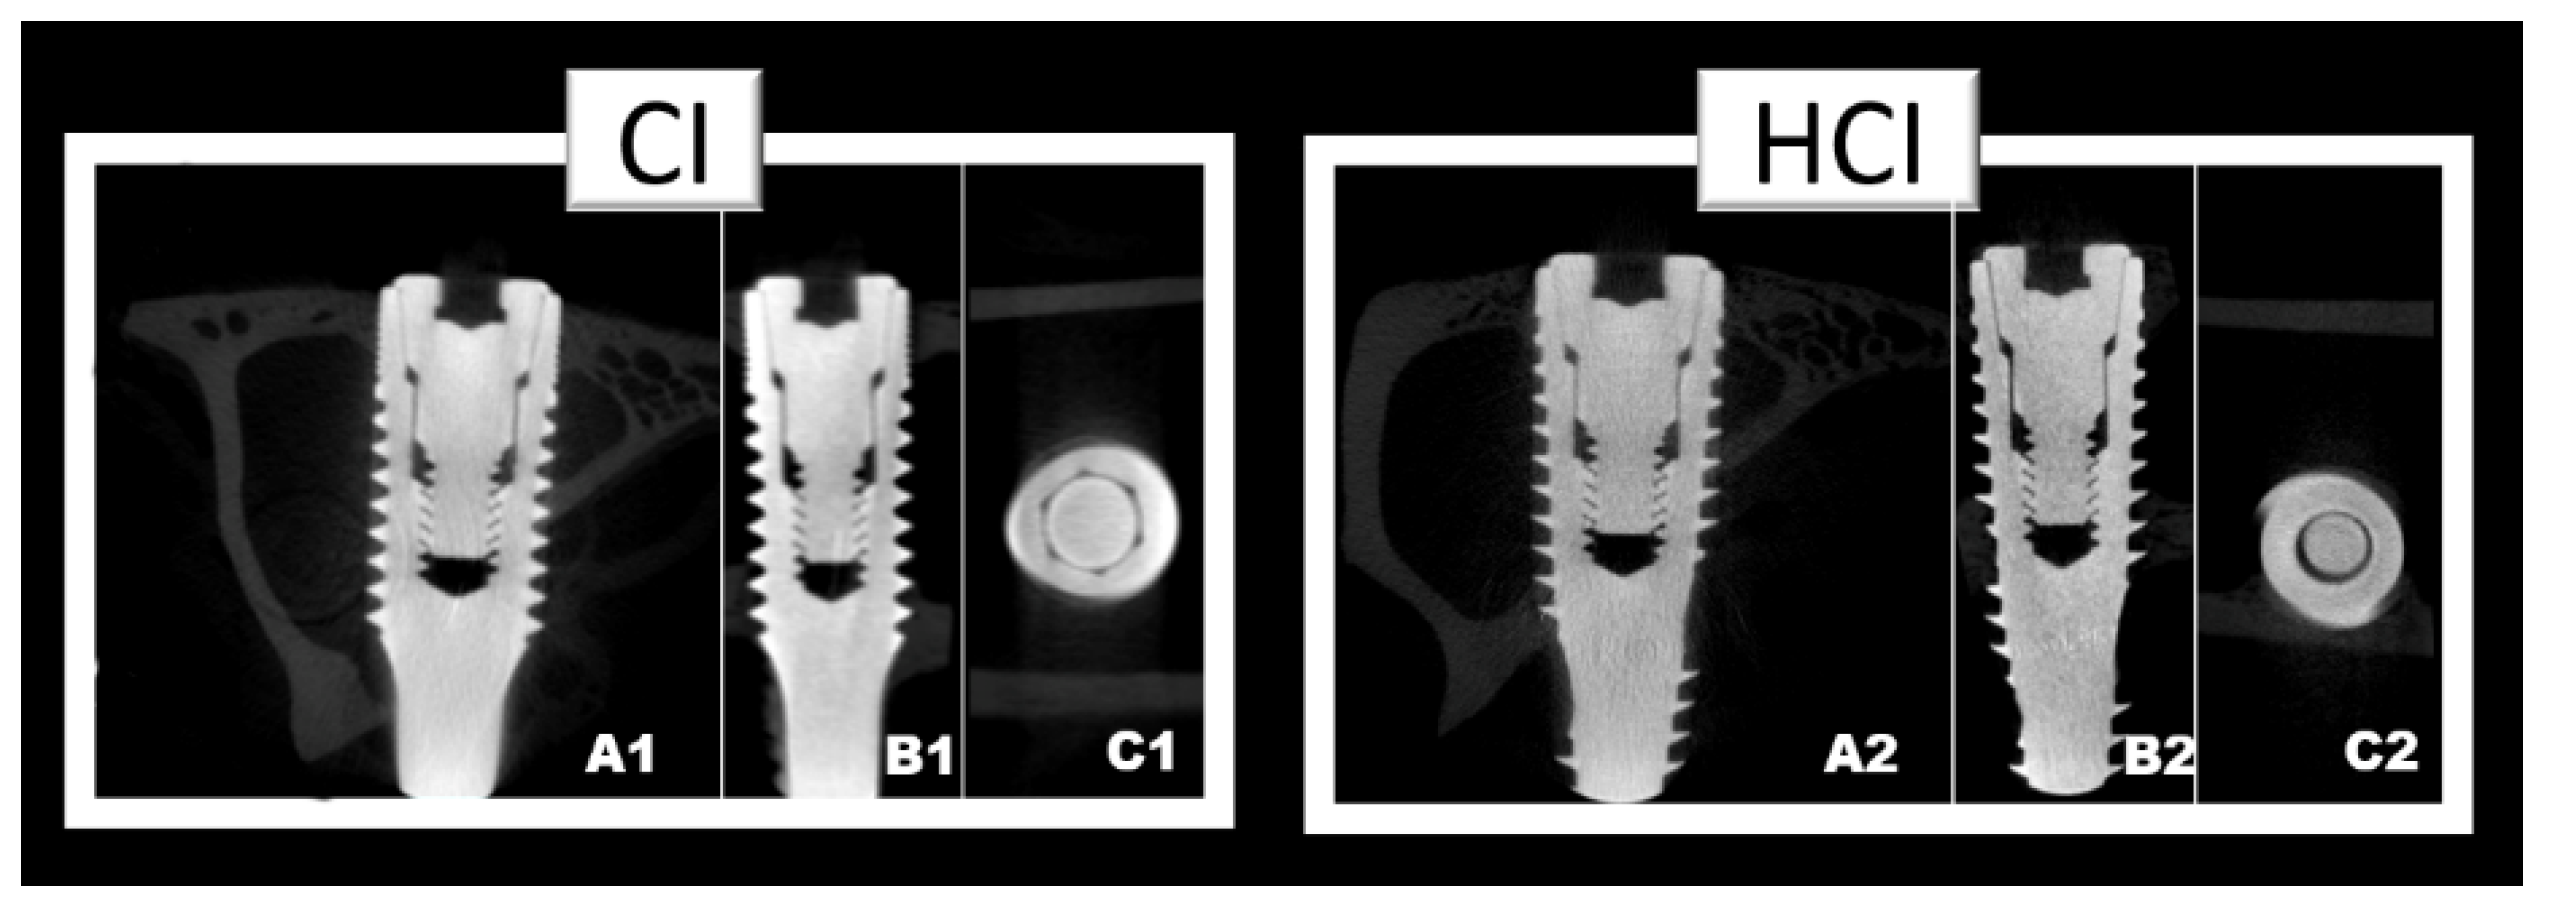

2.5. Microtomographic Analysis (µCT)

3.2. Microtomographic Analysis